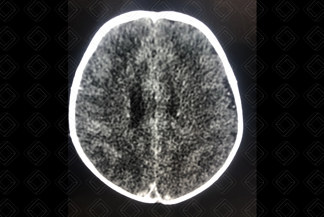

Texto alternativo para a imagem Figura 2. Créditos: Dra. Elazir Mota - Rio de Janeiro/RJ

Descrição das figuras 1 e 2: Tomografia computadorizada do crânio após a administração do contraste venoso. Sinal do delta vazio (seta vermelha): caracteriza-se pela falha de enchimento no interior do seio sagital superior, pela trombose.

• Tomografia computadorizada do crânio: Um dos grandes exames é angiotomografia venosa do crânio, que irá fazer adequado estudo dos seios venosos e das veias corticais. Permite ainda excelentes reconstruções tridimensionais (figura 1). Trombo no interior dos seios venosos, sinal do delta vazio (o sinal é caracterizado por uma área triangular central, que não realça - trombo propriamente dito, delimitada pela dura-máter captante do meio de contraste), congestão venosa e hemorragia subaracnoide. Na tomografia, o infarto ou edema cortical pode ser difícil visualização em fase mais precoce (aguda);